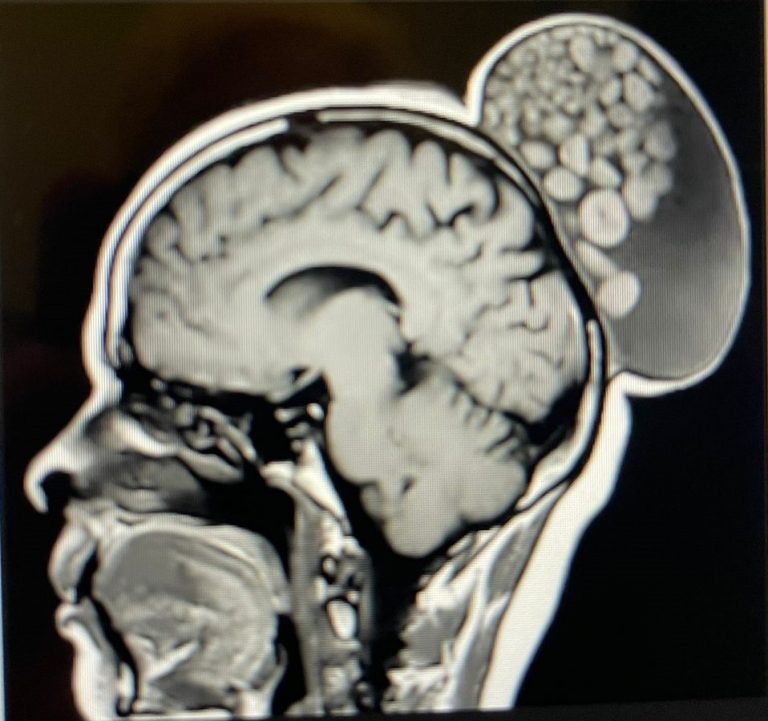

The woman’s scan showed a large cystic lesion at the backside of her scalp, which appeared like a hair bun on her head. Upon operating on the growth, doctors found it contained multiple nodules of varying sizes floating in the cyst, giving it a “sack of marbles” appearance,” the journal said. An MRI scan showed the cyst on the back of the woman’s head, like a fleshy made hair bun. Upon removing the growth, the medics noticed that the lesion was filled with “sebum-like material, hard spherules, and multiple strands of hair”.

“Histopathologic examination confirmed the diagnosis of a mature cystic teratoma, with elements from all three germ layers. There was no recurrence after six months of follow-up,” the journal said.

The “marbles” are spherical aggregates of keratin, fat, sebaceous material, fibrin, and hair floating within the fluid matrix of the cyst.

Though uncommon, the “sack of marbles” sign is considered pathognomonic of mature cystic teratomas in the head and neck, the journal said.